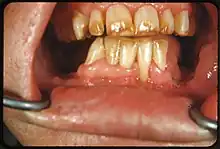

Tooth discoloration is abnormal tooth color, hue or translucency.[1] External discoloration is accumulation of stains on the tooth surface. Internal discoloration is due to absorption of pigment particles into tooth structure.[2][3] Sometimes there are several different co-existent factors responsible for discoloration.[4]

Extrinsic discoloration

Extrinsic discolorations are common and have many different causes.[10] The same range of factors are capable of staining the surface of restorations (e.g., composite fillings, porcelain crowns).[10] Some extrinsic discolorations that are allowed to remain for a long time may become intrinsic.[11]

- Calculus: Neglected plaque eventually calcifies, and leads to formation of a hard deposit on the teeth, especially around the gumline. The color of calculus varies, and may be grey, yellow, black or brown.[12]

- Tobacco: Tar in smoke from tobacco products (and also smokeless tobacco products) tends to form a yellow-brown-black stain around the necks of the teeth above the gumline.[12]